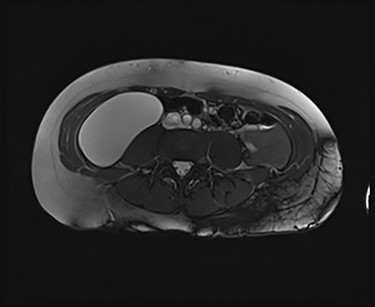

We present an extremely rare and isolated case of primary mixed serous and mucinous cystadenoma in a 49-year-old otherwise fit and healthy female patient. She was referred to our consultant with a history of discomfort on the right side of her abdomen for few years, which increased gradually with no other complains. The patient had further investigations conducted including computed tomography (CT) (Figs 1 and 2) that demonstrated the position and size of the lesion. The magnetic resonance imaging (MRI) revealed a large cystic lesion in the right retroperitoneal region shown in Figs 3 and 4. Her full blood count, inflammatory markers, urea and electrolytes and liver function tests were within the normal limit. Consequently, the patient had a laparoscopic resection of an isolated retroperitoneal cyst. At surgery, the cystic lesion seemed to be arising from mesentery and the lesion was dissected intact and completely excised. Histopathology revealed a benign mixed serous and mucinous cystadenoma as shown in Fig. 5. The patient was discharged from the hospital with no complications and fully recovered on follow-up review. Patient was discussed in a multidisciplinary team meeting and the recommendation was for no further management.

Serological investigations are not helping with providing a definitive diagnosis. Tumour markers such as, carbohydrate antigen (CA) 19–9, CA 15–3, CA 125, carcinoembryonic antigen (CEA), alpha feta protein have not been shown to be sensitive or specific. Some cases demonstrated an increase in CEA and CA 19–9 in associated with PRMC. However, these are isolated case studies. With regard to radiological investigation, the ultrasonography lacks specificity [11]. Radiological imaging, such as MRI and CT, plays an important role in describing and assessing the disease’s characteristics and the involvement of adjacent or distant structures of the mass. None of the modalities can exclude the malignant potential of the retroperitoneal masses [9], as the diagnostic value of CT and MRI is similar [12]. Predominantly male patients and the patients who present with solid nodules in the cyst on their radiology images have strong association with malignancy [13].